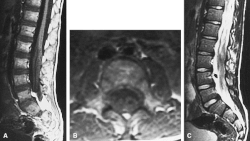

MRI compatible with Dejerine-Sottas type spinal nerve enlargement

On medical imaging, the peripheral and cranial nerves are enlarged by redundant connective tissue. On histology, this enlargement gives the nerves the appearance of an onion-bulb. Nerve excitability and conduction speed are reduced.[1]